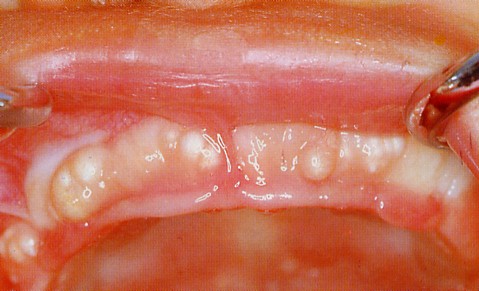

好発部位は歯肉、特に上顎前歯部の歯槽頂から唇側にわたるところで、広範囲に集中的に出現する傾向があります。

臼歯部では散発的にみられ、口蓋部にもみられることもあります。

白色ないし黄白色の光沢をもった半球状の硬い、粟粒大から小真珠大の大小の腫瘤としてみられます。

粘膜表面の近くに存在し、歯肉の表面からやや突出しているものが多いです。

2〜3個のものから通常は数多く発生するものが多く、そのために歯肉の表面が著しく凹凸不整の状態になっている

ものが多いです。

症例